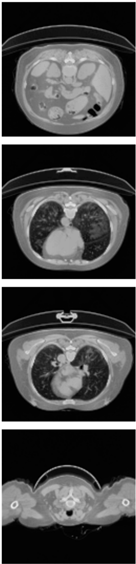

Furthermore, the CLAHE (Contrast Limited Adaptive Histogram Equalization) method is applied to overcome the contrast problems (noise and intensity inhomogeneity). CLAHE was used to intensify the contrast of the obtained images [47]. This method is a variant of AHE (Adaptive Histogram Equalization). CLAHE’s main objective is to determine the mapping for each pixel based on its neighborhood grayscale distribution using a transformation function that reduces contrast amplification in densely packed areas. In [48,49], CLAHE has shown its effectiveness in allocating displayed intensity levels in chest CT-scans. In Table 4, a comparison of the CT-scan slices before CLAHE was applied and after CLAHE was applied is shown.

Table 4.

Comparison before and after applying CLAHE preprocessing to CT-scan.